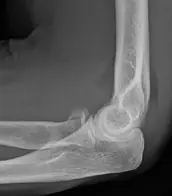

Fracture du coude